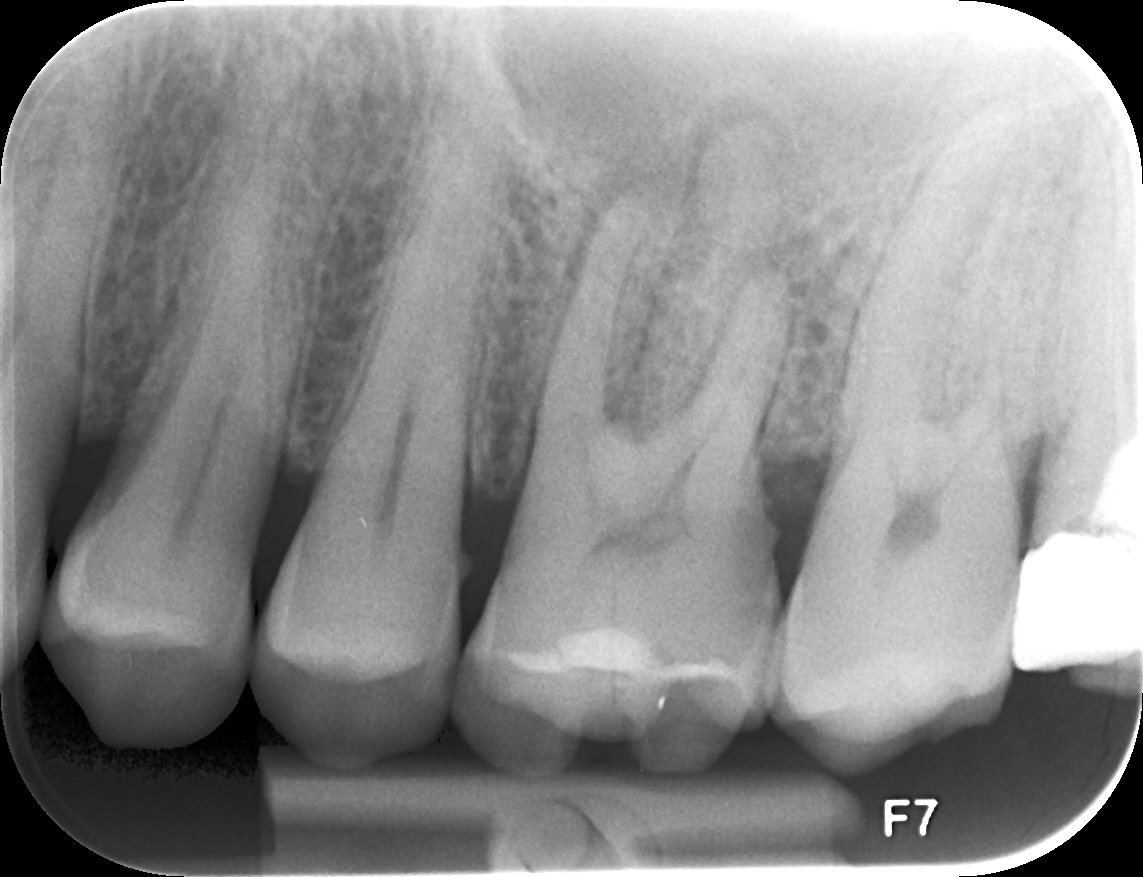

Domande di Dentisti-Italia.it | Pag. 638 (da 636 a 640)